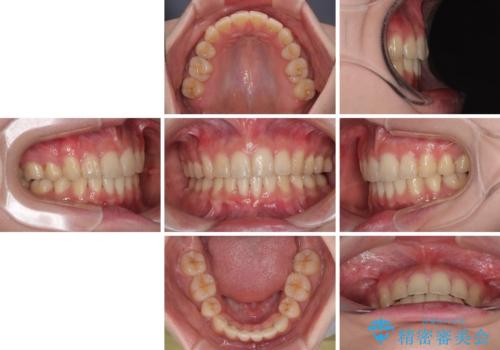

- 下顎の前歯が上顎の歯肉に咬みこむくらいに突出した上顎前歯を気にして来院された患者様です。

口元の突出感はないものの、上顎前歯が前方に傾斜して突出しており、前後に大きなズレがあり非常に深い咬み合わせとなっていました。

前突間を改善するため、上顎左右の第一小臼歯を抜歯してワイヤー装置にて矯正治療を行うこととしました。

深い咬み合わせは上顎前歯を引っ込ませる大きな障害となるため、咬み合わせの改善が非常に重要となります。やや期間はかかりましたが、当初狙った通りの仕上がりで治療を終えることができました。